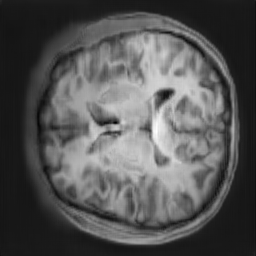

The study utilizes three 3D datasets, namely the GSP dataset[3], the LIDC-IDRI dataset[1], and the dataset employed for the Lung Nodule Analysis 2016 (LUNA16) challenge[21] which is a subset of LIDC-IDRI dataset. Samples from generated images at different stages of training are presented in Fig. 2 and Fig.3.

Figure 2: Synthetic images of CRF-GAN and HA-GAN at different iterations of training on GSP dataset